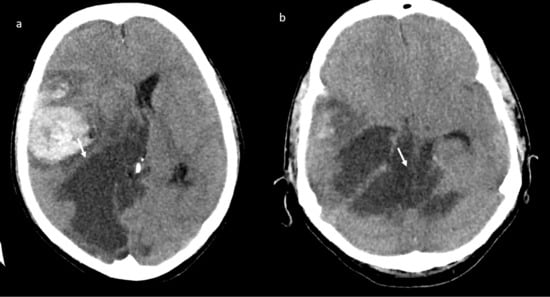

Brain magnetic resonance imaging (MRI) in the same day showed the presence of an acute basilar thrombosis (Figure 5a) associated with the superior sagittal sinus thrombosis (Figure 5b) with the delineation of hyperacute ischemic lesions in the vascular territory of the right posterior cerebral artery and of the perforating pontine branches (Figure 6).

Figure 5.

MR-angiography: acute basilar thrombosis associated with superior coronal (a) and sagittal (b) sinus thrombosis.